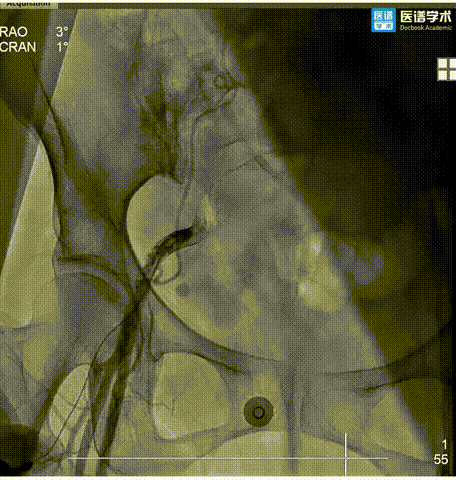

2.主动脉根部造影,瓣上钙化清晰,未见明显反流影。

3.直头导丝跨瓣,通过交换导丝将猪尾导管引入左室,测得跨瓣压差约99mmHg。